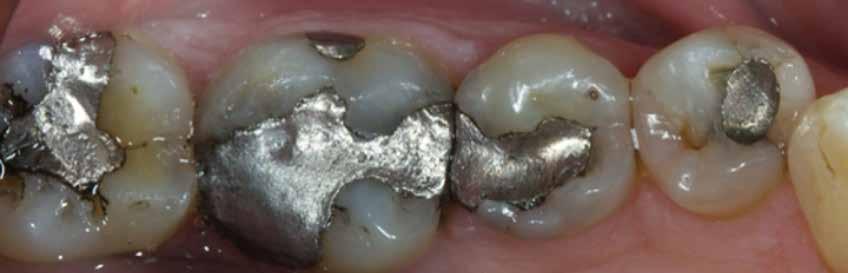

2. ábra: A páciens egy nem megfelelő I. osztályú ezüst-amalgám töméssel és II. osztályú szuvasodással jelentkezett. A fog izolálása kofferdám alkalmazásával történt.

3. ábra: A preparálás, a bondozás és a kompozit felvitele után. (Megjegyzés: némi kompozit túlfolyás látható a mesiális doboz axiális falain).

4. ábra: A durva finírozás után a restauráció pereme sima és anatómiailag is megfelelő.

Klinikai példa az 2–4. képeken látható.